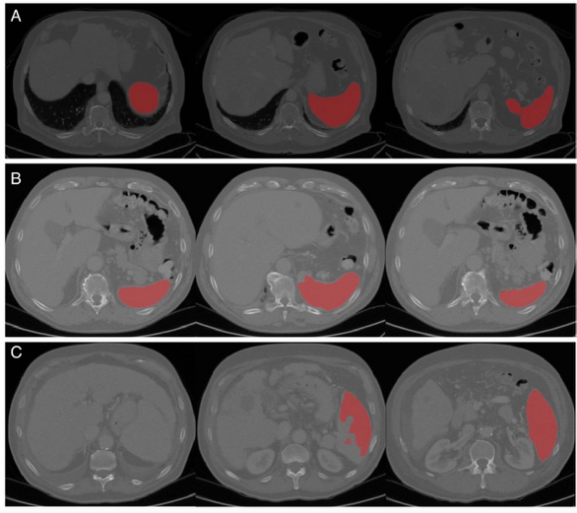

圖 算法性能的代表性圖像(從左到右是脾臟上部、中部和下部的圖像)。A完美的分割,B可接受的分割(中間有輕微的分割錯(cuò)誤),C差的分割(上部有主要的分割錯(cuò)誤,有吻合的肝臟和脾臟現(xiàn)象)